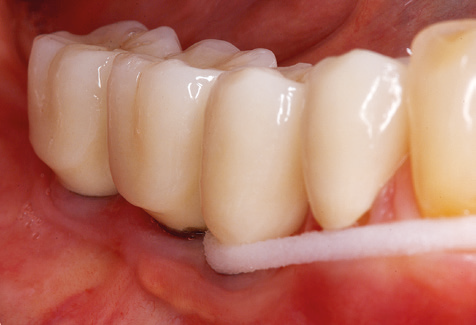

A 52-year-old patient presented in our clinic for the first time in 2004 following tooth loss in the third quadrant, expressing a desire for a new prosthetic restoration. Periodontal and radiological diagnostics revealed the need for extensive periodontological treatment. In addition, teeth 48, 28 and 27 were attributed a very poor prognosis and were subsequently extracted (Fig. 1). Following the successfully completed, systematic periodontological treatment, a fixed dental implant was inserted with the introduction of five implants in tooth regions 35, 36, 37, 46 and 47. Prosthetic treatment of the natural teeth was effected with veneered zirconium dioxide ceramic crowns; the implants were composed of two-piece, individual zirconium dioxide abutments and similarly veneered crowns made of a zirconium dioxide ceramic (Cercon base colored, Dentsply Sirona Lab). Definitive insertion of the prosthetic restoration occurred in 2005.

Due to the presence of periodontal disease, SPT was performed every three months in the first years following the insertion. The patient demonstrated a high degree of motivation and good compliance. The pocket depths recorded annually revealed a stable periodontal situation with a BOP index of below five per cent. On the basis of the stable periodontal situation and good cooperation on the patient’s part, the recall interval was extended to every six months as of the sixth year of the prosthetic function phase. Following the change in the recall interval, the respective annual documentation of the periodontal status continued to reveal a stable periodontal situation with no increase in the pocket depths and a BOP index below five per cent (Fig. 2a and b).

The ten-year check-up revealed no indications of advancing clinical attachment loss or peri-implant bone substance loss (Fig. 3).

The patient continues to visit the clinic every six months for SIT. In the following, the patient is taken as an example for demonstrating the individual working steps in a structured SPT session as it has been performed with barely any modifications over the last 12 years. Of course, some new materials and devices have been integrated into the concept over the years. This clinical case report presents the current material and device concept.

Standardised and regular risk-adapted care in the scope of SPT is the key to treatment success for the clinical long-term success in periodontically compromised patients. This is particularly true for patients fitted with implants following successfully completed periodontal treatment (Fig. 11a and b).